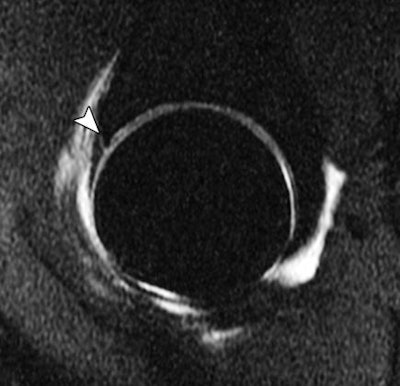

| Sagittal T1-weighted MR arthrography image with fat saturation shows tear of anterior acetabular labrum (arrowhead) in 36-year-old woman. All images republished with permission of the American Roentgen Ray Society from AJR, August 2012, Vol. 199:2, pp. 413-418. |

Another 34.8% (8/23) of all findings represented fibrocartilaginous injuries, including medial meniscus tears (8.7%), acetabular labrum tears (8.7%), glenoid labrum tears (8.7%), and lumbar disk annular tears with disk extrusion (8.7%). Transient patellar dislocation was found in two (8.7%) of the 23 cases.